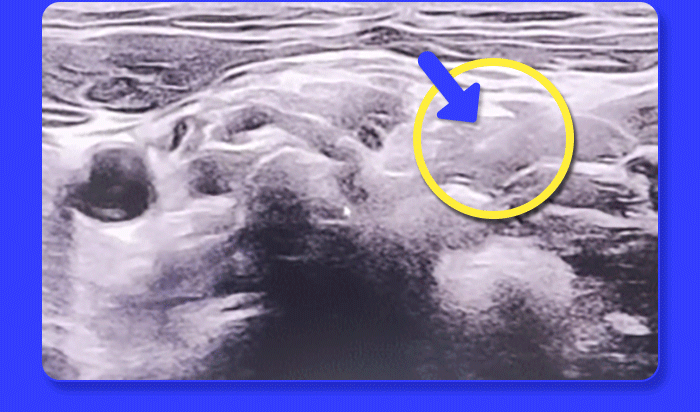

자생 초음파 약침- 눈에 보이지 않던 통증의 원인, 초음파로 정확히 확인 후 치료합니다. / 초음파 진단 보조로 더 정밀한 약침 치료, ‘초음파 약침 치료’란? - 초음파를 활용한 현대적 진단 기술과 한의학적 약침 치료 원리를 결합하여 경혈과 병변 부위에 정밀하게 약침을 시술하는 한방 치료법

왜 초음파를 보면서 약침을 놓을까요? - 정확한 병변 부위에 약침 주입 치료 효과 증대 ▲ - 실시간 영상 진단 보조로 시술 안정성/ 정확도 강화 - 약침 효능 집중 전달 항염증, 조직 재생 촉진 -초음파 약침 치료 대상 통증이 심한 중증 척추 질환이나 퇴행성 질환, 급성 통증으로 빠른 치료가 필요한 경우 등 다양한 케이스에 적용 가능 V 허리디스크, 목디스크, 척추관협착증 V 어깨 통증, 오십견, 회전근개 손상 V 퇴행성 관절염, 무릎 관절 통증 V 팔꿈치·손목 통증(테니스엘보 등) V 만성 근육통, 반복되는 통증 / 병변 부위를 보고 정확히 시술하는 자생 초음파 약침 - 약침 치료는 한약 성분을 정제한 약침액을 환부에 직접 주입하는 치료로, 환자의 증상과 병변 상태에 따라 의료진이 적절한 치료 방법을 선택합니다. 일반약침 vs 초음파약침 비교표 / 한의학적 지식 & 초음파 진단 기술 겸비 숙련된 의료진 시술 - 미국 근골격계 초음파 자격증(RMSK) 보유 - 척추·관절 치료에 대한 풍부한 임상 경험을 가진 의료진의 섬세한 시술로 치료 효과를 높입니다.